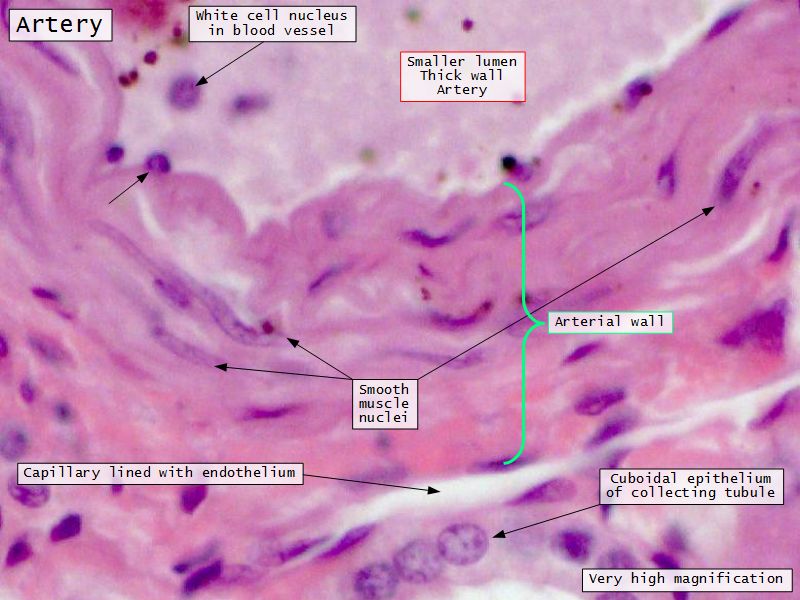

Blood flow

- Efferent arteriole

- Smooth muscle in media

- Capillaries

- Fenestrated

- Afferent arteriole

- Smooth muscle in media

Collecting tubule

- Cuboidal to columnar epithelium

- Distinct lateral borders